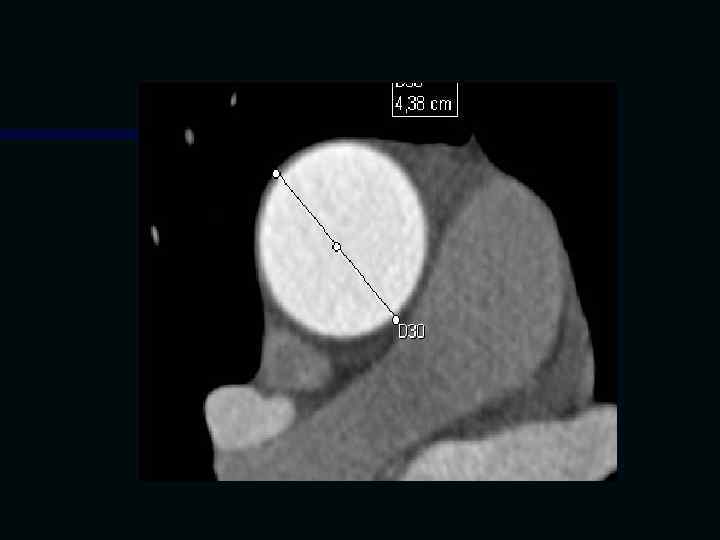

Исследование сосудов грудной клетки